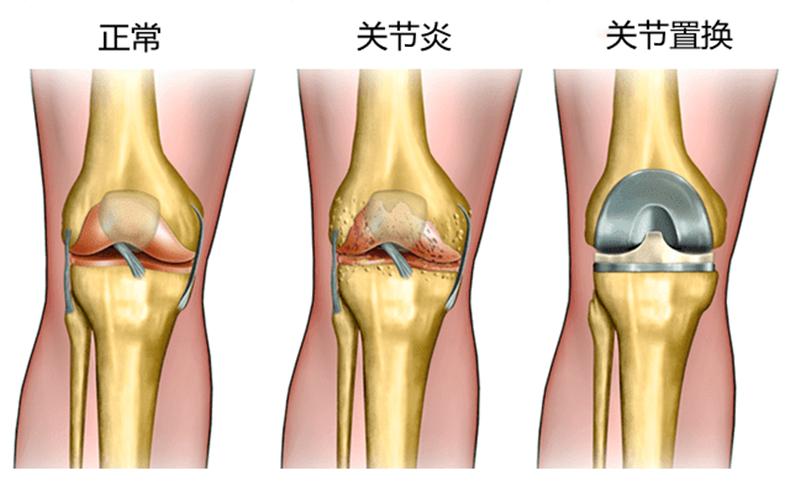

什么是人工膝关节置换手术?

膝关节主要由三块骨头组成:大腿骨(股骨),小腿骨(胫骨),膝盖骨(髌骨)。这些骨头的接触面(软骨)会随着时间产生磨损,进而导致关节炎,或者其他原因引起疼痛和肿胀。通过减肥,物理治疗,药物,注射和支具,一切保守疗法都无效的前提下,就可以考虑进行膝关节置换手术。

人工膝关节由金属和聚乙烯构成,置换手术也并非切掉整块骨头,而是用人工假体置换关节的表面,有些像戴个牙套,也可以根据病情,进行全膝关节置换和部分膝关节置换。这种手术的目的在于缓解疼痛,提高生活质量,改善膝关节功能。原则上适合所有年龄段的人,但由于人工关节有使用寿命,中老年患者进行置换得较多。医生也可能建议一些年轻患者推迟手术。